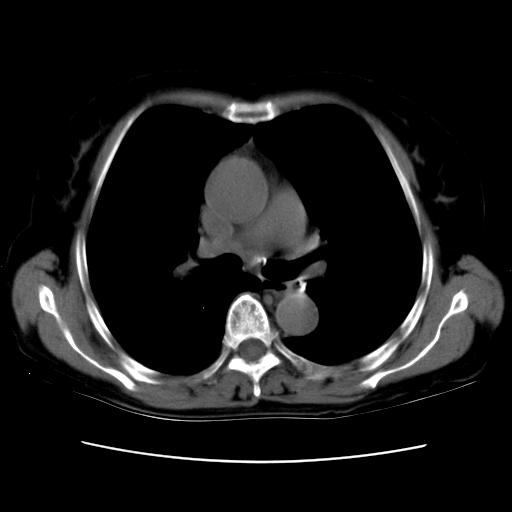

以下是引用卜一在2007-9-18 14:41:00的发言:[br]右肺肿块:毛刺+胸膜凹陷征+供血血管+浅分叶+强化。支持:周围性肺癌 !另:左侧甲状腺腺瘤!

以下是引用夏季在2007-9-18 11:00:00的发言:[br]1。右肺肿块,周围有短毛刺,肺门侧有血管与其相连,胸壁侧有胸膜凹陷征,考虑周围性肺癌 2。左侧甲状腺软组织肿块,内有高密度钙化灶,考虑左侧甲状腺腺瘤。